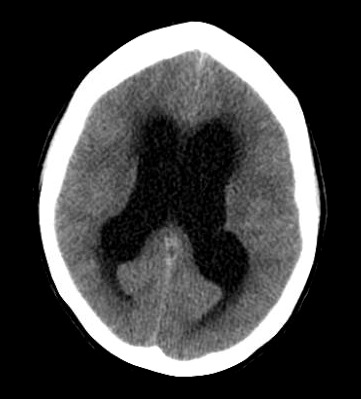

Considerations were given to possible adverse drug reaction to Promethazine, other toxic or infectious etiologies, or structural lesions. Laboratory studies were within normal limits. While waiting to receive a CT scan of her brain, a bedside ocular ultrasound was performed which demonstrated an optic nerve sheath diameter less than 5 mm. without evidence of papilledema. Her CT brain without IV contrast demonstrated dilated lateral ventricles with associated transependymal edema. (Figure 1) An emergent MRI of the brain without contrast was completed to identify a colloid cyst at the level of the Foramen of Monro measuring 1.3 x 1.3 cm. (Figure 2) There was marked obstructive hydrocephalus and cerebral sulcal effacement seen in the image consistent with cerebral edema. The patient was admitted to our hospital for evaluation by the Neurology and Neurosurgery teams.